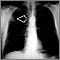

Enfermedad pulmonar

Es cualquier problema en los pulmones o que impide que éstos trabajen apropiadamente. Existen tres tipos principales de enfermedad pulmonar (neumopatía):

1. Enfermedades de las vías respiratorias: estas enfermedades afectan los conductos (vías aéreas o respiratorias) que permiten que el oxígeno y otros gases entren y salgan de los pulmones. Estas enfermedades causan un estrechamiento u obstrucción de las vías respiratorias y abarcan asma, enfisema, bronquiectasia y bronquitis crónica. Las personas con enfermedades de las vías respiratorias con frecuencia dicen que sienten como si "trataran de exhalar a través de una pajilla".

2. Enfermedades del tejido pulmonar: afectan la estructura del tejido pulmonar. La cicatrización o la inflamación del tejido hace que los pulmones no se puedan expandir totalmente ("enfermedad pulmonar restrictiva"). Esto hace que para los pulmones sea más difícil inhalar oxígeno (oxigenación) y liberar dióxido de carbono. Las personas con este tipo de trastorno pulmonar a menudo dicen que sienten como si "llevaran puesto un suéter o un chaleco demasiado apretado" que no les permite tomar una respiración profunda. La fibrosis pulmonar y la sarcoidosis son ejemplos de enfermedades del tejido pulmonar.

3. Enfermedades de la circulación pulmonar: afectan los vasos sanguíneos en los pulmones. Son causadas por coagulación, cicatrización o inflamación de dichos vasos. Estas enfermedades afectan la capacidad de los pulmones para captar oxígeno y liberar dióxido de carbono e igualmente pueden afectar la actividad cardíaca.

Muchas enfermedades pulmonares involucran una combinación de estos tres tipos.